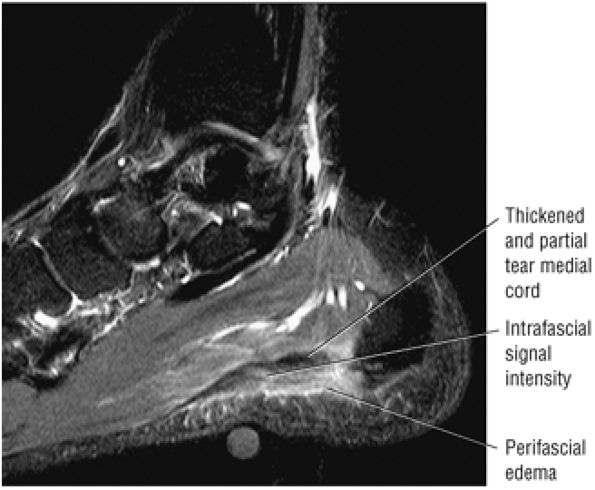

FIGURE 5.137 ● Normal MR appearance of the spring ligament complex. (A) Axial PD image demonstrates the lateral and intermediate calcaneonavicular ligaments originating from the notch between the anterior and middle articular facets of the calcaneus. The lateral calcaneonavicular ligament inserts on the navicular beak. (B) Axial PD image a few slices superior demonstrates the superomedial calcaneonavicular ligament deep to the posterior tibial tendon as it passes along the lateral aspect of the talar head toward its attachment to the dorsal aspect of the navicular tubercle. (C) Coronal T1-weighted image at the level of the talar head demonstrates the superomedial calcaneonavicular ligament deep to the posterior tibial tendon along the lateral aspect of the talar head.

|

![]() |

FIGURE 5.138 ● Pathologic appearances of the superomedial calcaneonavicular ligament. (A) Coronal FS PD image with fat saturation demonstrates a thickened and mildly edematous superomedial calcaneonavicular ligament in a patient who also had posterior tibial tendon strain. (B) Axial FS PD image with fat saturation demonstrates a thickened and edematous superomedial calcaneonavicular ligament in the setting of a partial posterior tibial tendon tear. (C) Axial PD image demonstrates a heterogeneous and irregular superomedial calcaneonavicular ligament in the setting of posterior tibial tendinosis and pes planus.